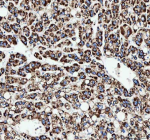

IHC analysis of CAMKK2 using anti-CAMKK2 antibody. CAMKK2 was detected in a paraffin-embedded section of human liver cancer tissue. Heat mediated antigen retrieval was performed in EDTA buffer (pH 8.0, epitope retrieval solution). The tissue section was blocked with 10% goat serum. The tissue section was then incubated with 2 ug/ml rabbit anti-CAMKK2 antibody overnight at 4oC. Peroxidase Conjugated Goat Anti-rabbit IgG was used as secondary antibody and incubated for 30 minutes at 37oC. The tissue section was developed using an HRP secondary and DAB substrate.